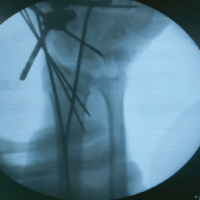

Fluoroscopic guiding is employed to percutaneously introduce Schanz pins into the bone. The positioning of these pins is done with great care to prevent any damage to neurovascular structures and to ensure the best possible stability. Subsequently, the pins are linked to an ExFix structure that can be modified to attain accurate alignment and reduction of the fracture.

After positioning the frame, the surgeon skillfully adjusts the broken pieces of the fracture to realign them with the body’s natural structure. This reduction is confirmed with the use of fluoroscopy. If necessary, more modifications are implemented to the fixator in order to attain the desired alignment. Subsequently, the fixator frame is firmly fastened to ensure the maintenance of the decrease.

After the surgery, the wrist is placed in a splint or cast to prevent movement and support the initial healing process. Follow-up involves the use of sequential radiographs to evaluate the healing of the fracture and the correct positioning of any surgical implants. Dorsal distraction plating provides strong stabilization, allowing for prompt movement and restoration of function. Physical therapy is started once X-ray imaging confirms that the wrist has healed enough to regain its range of motion and strength. Subsequently, after the removal of the implant, adhesiolysis is carried out during the surgery to regain the mobility of the wrist joint. Dorsal distraction plating X-rays (Fig. 1, 2, 3, 4). ExFix X-rays (Fig. 5, 6, 7, 8, 9).